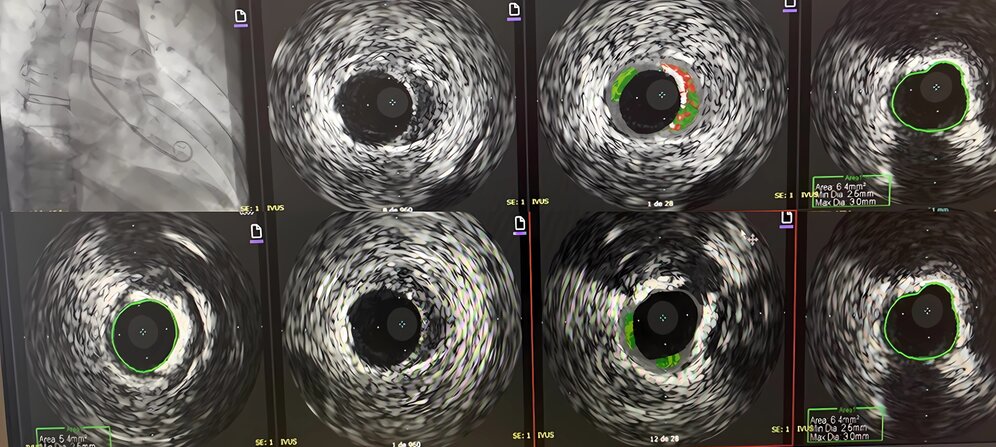

Day 2 – Coronary Angiography and IVUS

Coronary angiography, performed via left radial artery access, demonstrated minimal, non-obstructive coronary artery disease. The right coronary artery was dominant, and the left circumflex artery appeared angiographically normal. A mild 20% ostial narrowing of the left main coronary artery was observed. Intravascular ultrasound (IVUS) confirmed mild, calcified stenosis (30–40%) in the left anterior descending artery, with a minimal luminal area of 5.4 mm² (Figure 3). No flow-limiting lesions were identified.

Figure 3. Coronary angiography and intravascular ultrasound (IVUS) revealed non-obstructive coronary artery disease. Mild calcified stenosis (30–40%) is observed in the proximal left anterior descending artery, with a minimal luminal area of 5.4 mm².